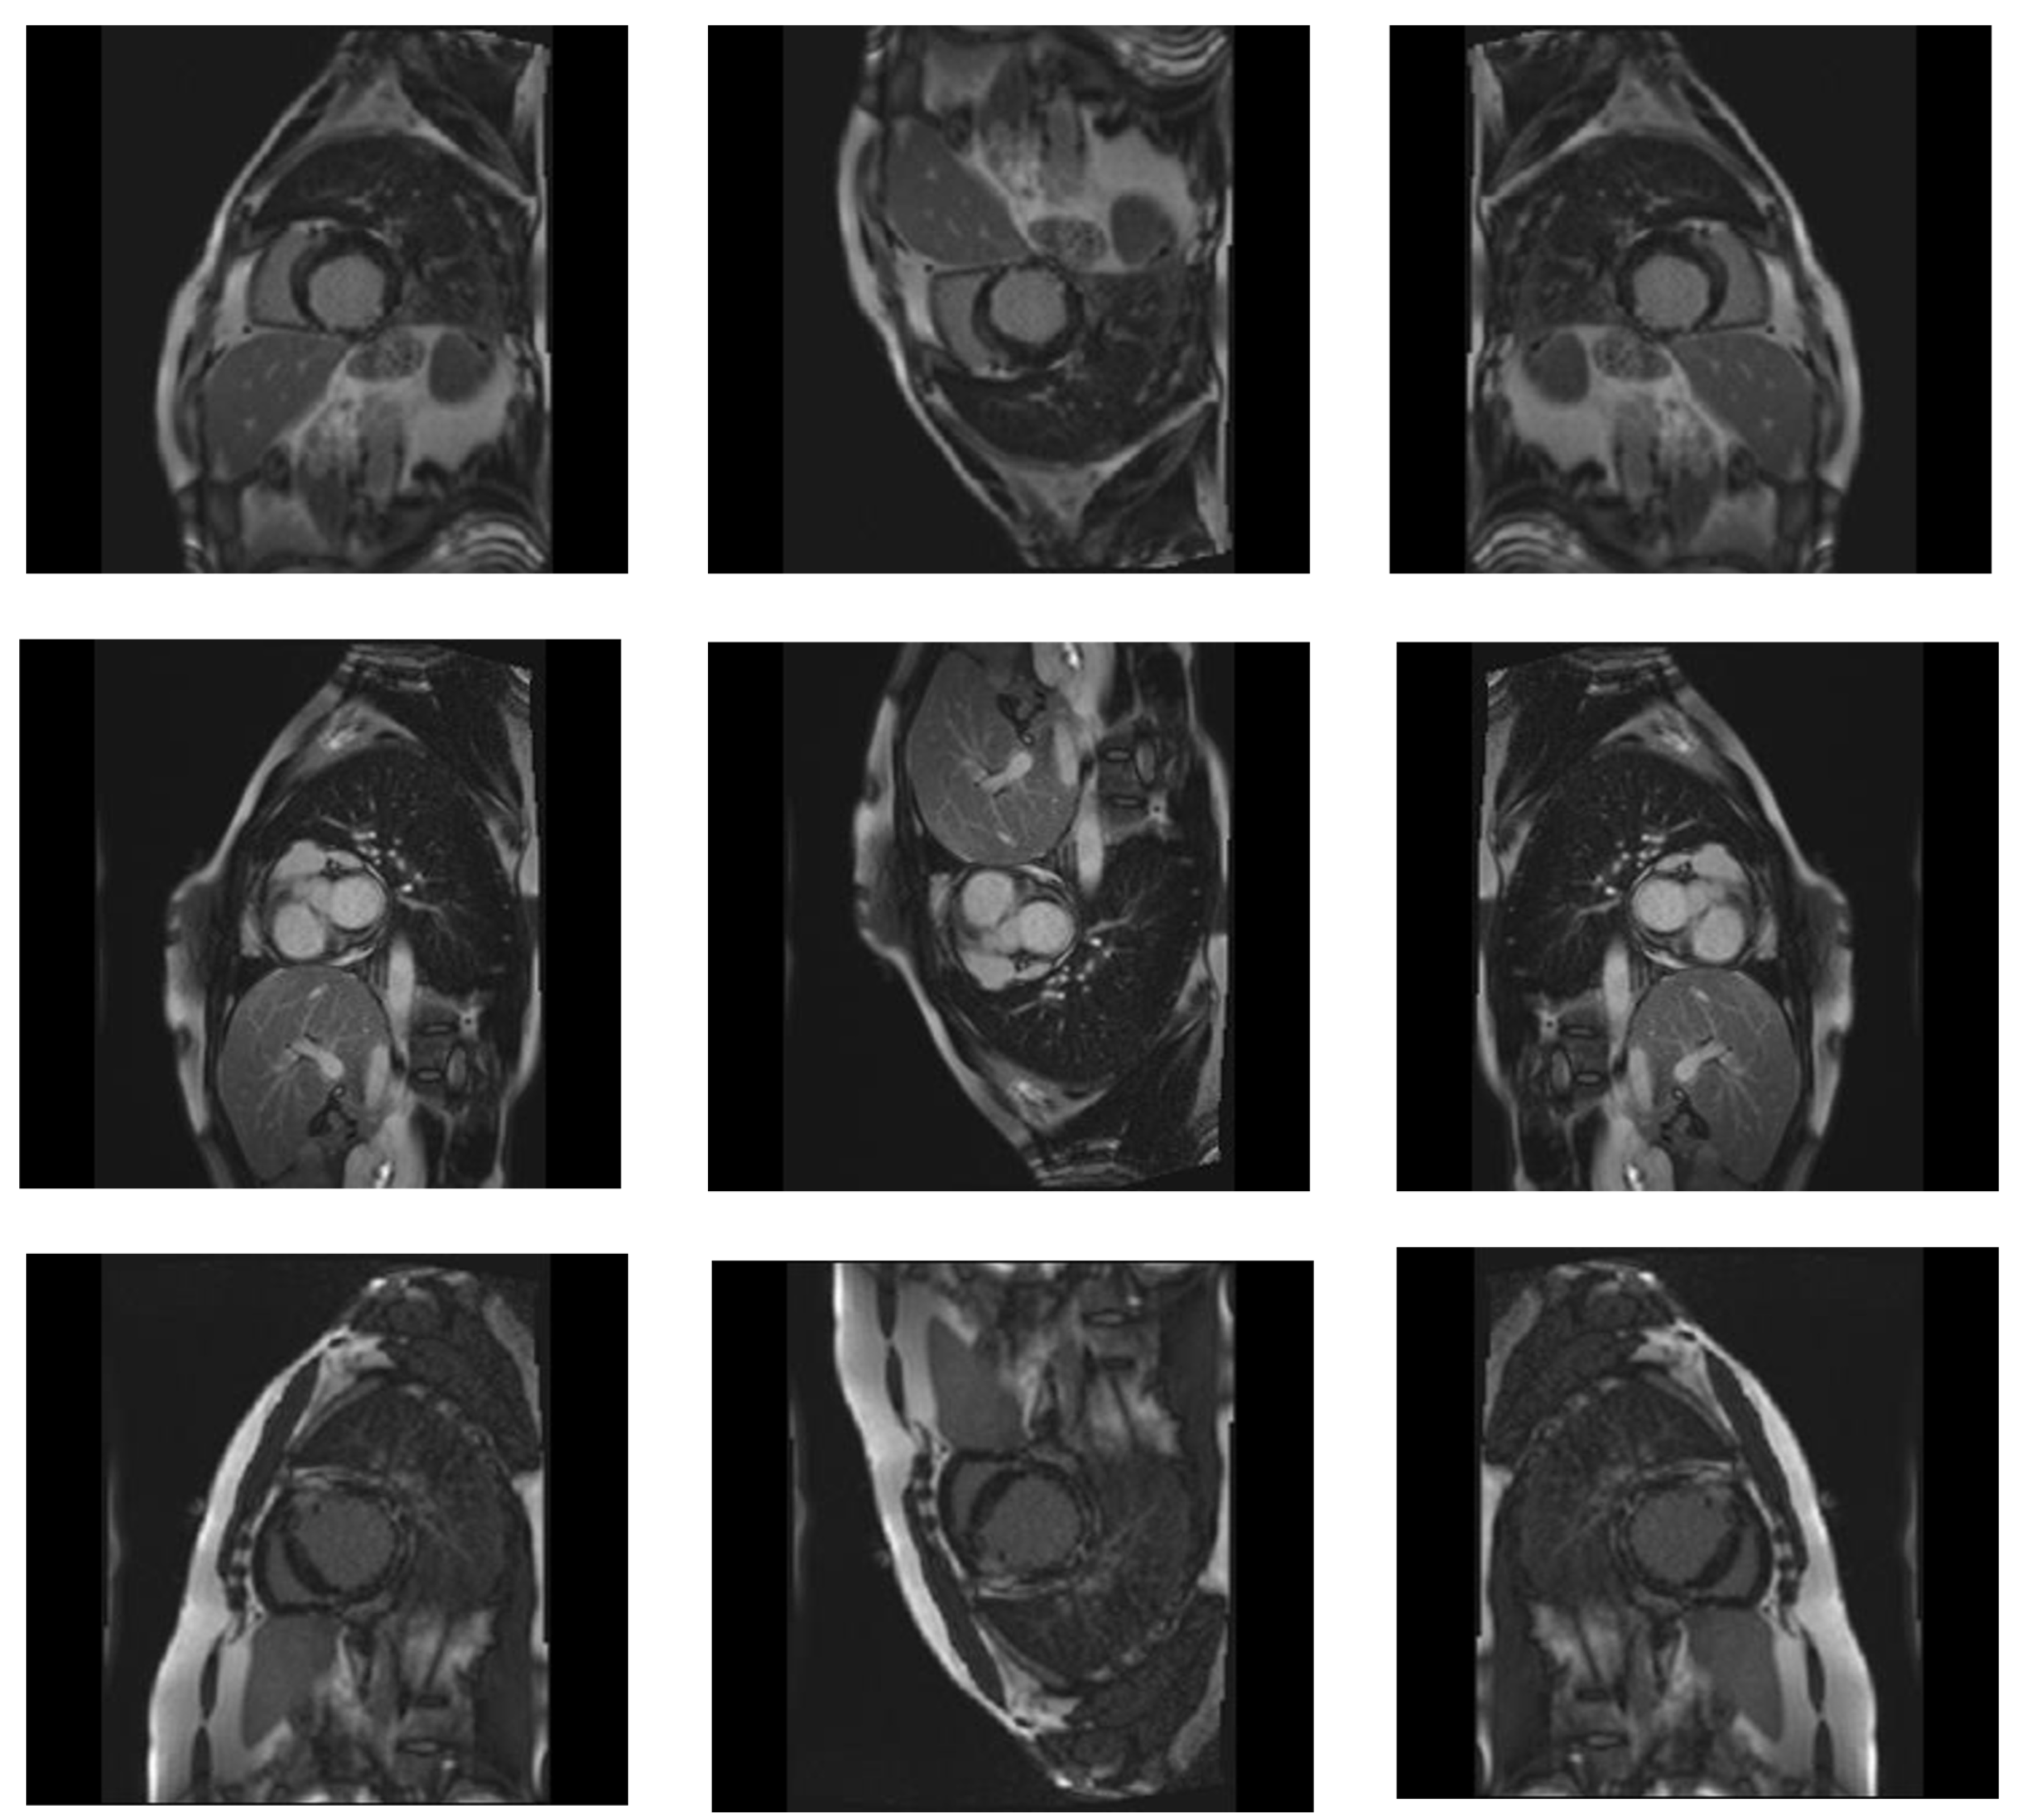

3.1. Dataset

3.2. Preprocessing